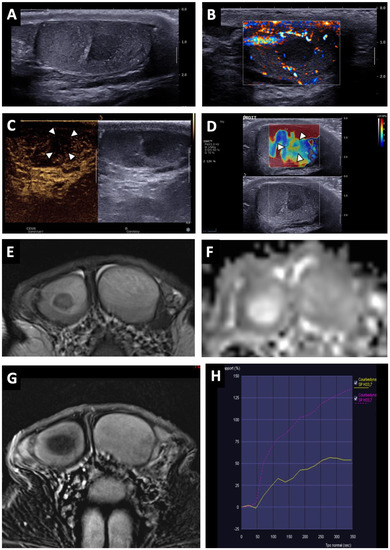

Figure 4. Partially regressed seminoma of the right testis in a 52-year-old man (symptomatic metastatic retroperitoneal nodes). Coronal T2W image showing a nodule with ill-delineated margins in hyposignal (white arrow) (A). Coronal reconstruction of an ADC map showing a focal elevation of ADC values (black arrowheads) with a central area of restriction (in black) (B). Before injection, no focal abnormality was visible on the axial T1W sequence (C). After intravenous injection of the contrast agent, a large area of reduced enhancement was visible (overlapping the lesions compared to the T2W images) with a central enhanced nodule (white arrow) (D). Axial post-injection T1W image of the left testis showing the usual testicular parenchymal enhancement (E). Pathological analysis revealed a 5 mm residual seminoma within a 2 cm fibro-hyaline patch.

BOTTs appeared as round or oval nodules (81%) (Figure 3 and Figure 4) or a focal area with irregular boundaries (19%) on the T2 sequences (hyposignal). No lesions were visible on the T1 sequences (isosignal) (Figure 4C).

The diffusion-weighted sequences showed nodular areas of reduced signal with increased ADC values (mean value: 2 ± 0.3 × 10−3 mm2/s) (Figure 2E and Figure 3F) compared to contralateral parenchyma (mean value: 1.3 ± 0.3 × 10−3 mm2/s) in all patients (significant difference, p < 0.01). The mean ADC ratio was 1.6 ± 0.3. Within these areas with increased ADC values, a restrictive nodule (Figure 4B) was detected in six of the seven patients that were diagnosed with a partially regressed testicular tumour.

Dynamic contrast-enhanced sequences showed areas of reduced enhancement in all cases. The size of this area matched that of the lesion on the T2 sequences (Figure 3G) in 11 patients (26.2%), and in 31 patients (73.8%) it overlapped the lesion with reduced enhancement extending to the peripheral parenchyma (Figure 2F and Figure 4D). In the cases of partial tumour regression, dynamic contrast-enhanced sequences revealed early and strongly enhanced focal abnormalities within areas of reduced enhancement, corresponding to nodules in six patients (Figure 4D), and an ill-delineated area with increased enhancement in one (corresponding to the patient in whom no focal abnormality that was suggestive of a viable tumour was found upon US examination).

A lymphoplasmacytic infiltrate in the fibrous tissue was reported in 28 cases (58%), was absent in one and was not specified in the others. In all cases there were completely hyalinized tubules that were mainly associated with a “Sertoli cell only” pattern peripheral to the scar. Impaired spermatogenesis was seen in all the patients. Intratubular germ-cell neoplasia (IGCN) was found in nine patients (18.8%) peripheral to the area of scarring, which was associated with partial tumour regression in four cases. In the six cases of partial tumour regression, the lesions found were pure seminomas.